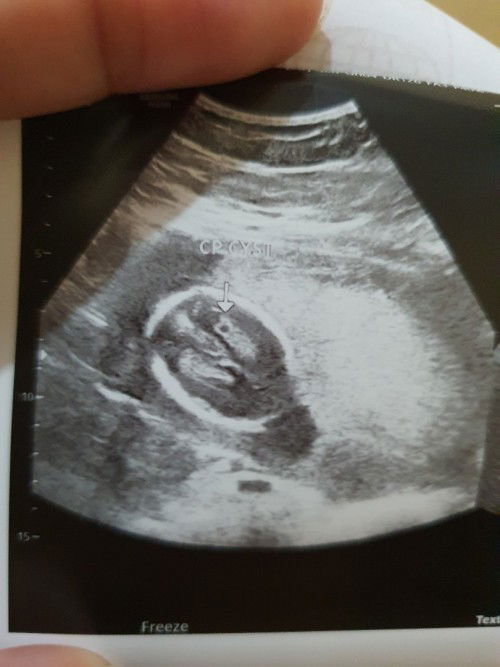

Choroid Plexus Cyst

Hi moms anyone na nakitaan ng Choroid Plexus Cyst si baby sa ultrasound. Currently on 2nd trimester. I want to know if nawawala din po ba to? tysm#pleasehelp #pregnancy